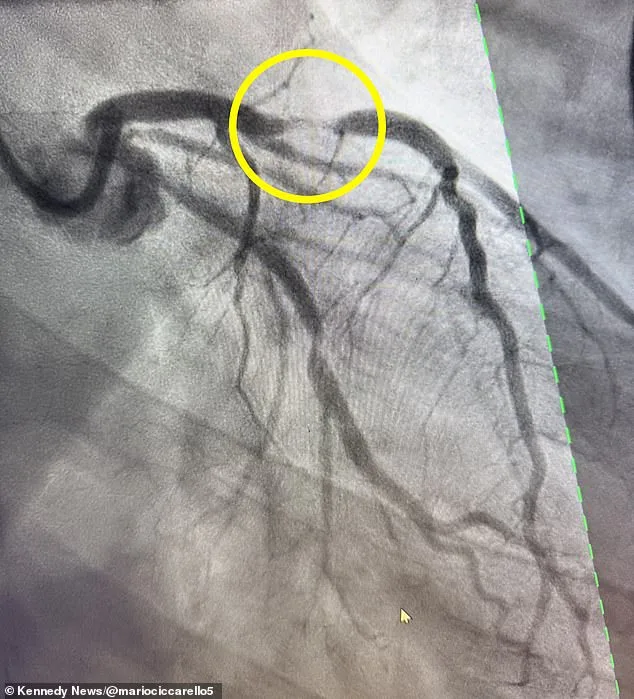

At the hospital, doctors discovered a 95% blockage in his left anterior descending artery, a condition known as a 'widow-maker' heart attack. The term reflects the grim statistic that only 12% of patients survive such an event, as the blockage can cause catastrophic damage to the heart's pumping chamber. This type of heart attack, while more common in men in their 40s, can also affect women over 50. The discovery underscored the unpredictability of cardiac emergencies, even for those who appear to be in peak health.

Despite the grim odds, Ciccarello's life was saved by the insertion of two stents, which restored blood flow to his heart. Now on blood thinners and undergoing genetic testing, he is using his platform to raise awareness about the signs of a heart attack. Symptoms such as chest pain, shortness of breath, dizziness, and fatigue are often overlooked, even by those who lead healthy lifestyles. His experience serves as a stark reminder that heart attacks can strike anyone, regardless of age or fitness level.